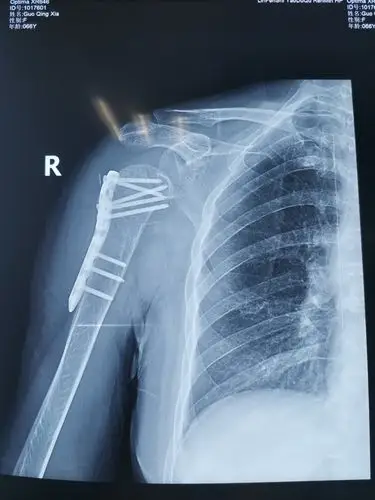

术后右肩关节正位片